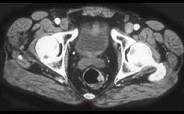

问题 男性,41岁,血便,肛诊触及左侧直肠壁一质硬小结节,结合CT所见应考虑为()

选项 A.直肠腺瘤 B.直肠癌 C.直肠息肉 D.直肠转移瘤 E.直肠间质瘤

答案 B